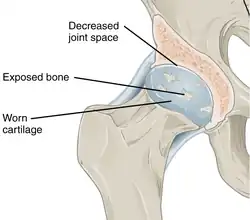

With osteoarthritis, the cartilage becomes worn away. Spurs grow out from the edge of the bone, and synovial fluid increases. Altogether, the joint feels stiff and sore. -